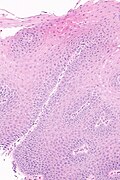

Micrograph showing histology compatible with gastroesophageal reflux disease. H&E stain. | |

| LM | basal cell hyperplasia (> 3 cells thick or >15% of epithelial thickness), papillae elongated (papillae reach into the top 1/3 of the epithelial layer), inflammation, esp. eosinophils, lymphocytes with convoluted nuclei ("squiggle cells"), +/-intraepithelial edema, +/-apoptotic cells, +/-glycogenation |

| LM DDx | intestinal metaplasia (Barrett's esophagus), eosinophilic esophagitis, acute esophagitis |

- Basal cell hyperplasia;[5] > 3 cells thick or >15% of epithelial thickness.

- Papillae elongated; papillae reach into the top 1/3 of the epithelial layer.[6]

- Inflammation, esp. eosinophils, lymphocytes with convoluted nuclei ("squiggle cells").

- +/-Intraepithelial edema.

- +/-Apoptotic cells.[7]

- +/-Glycogen - cytoplasm cleared (white).[8]